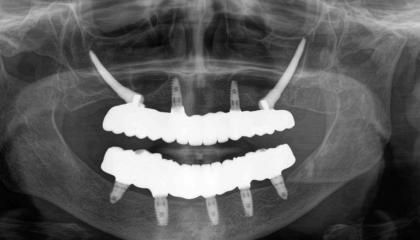

Zirconia bridge on Southern DC Implants

Zirconia Implants

After